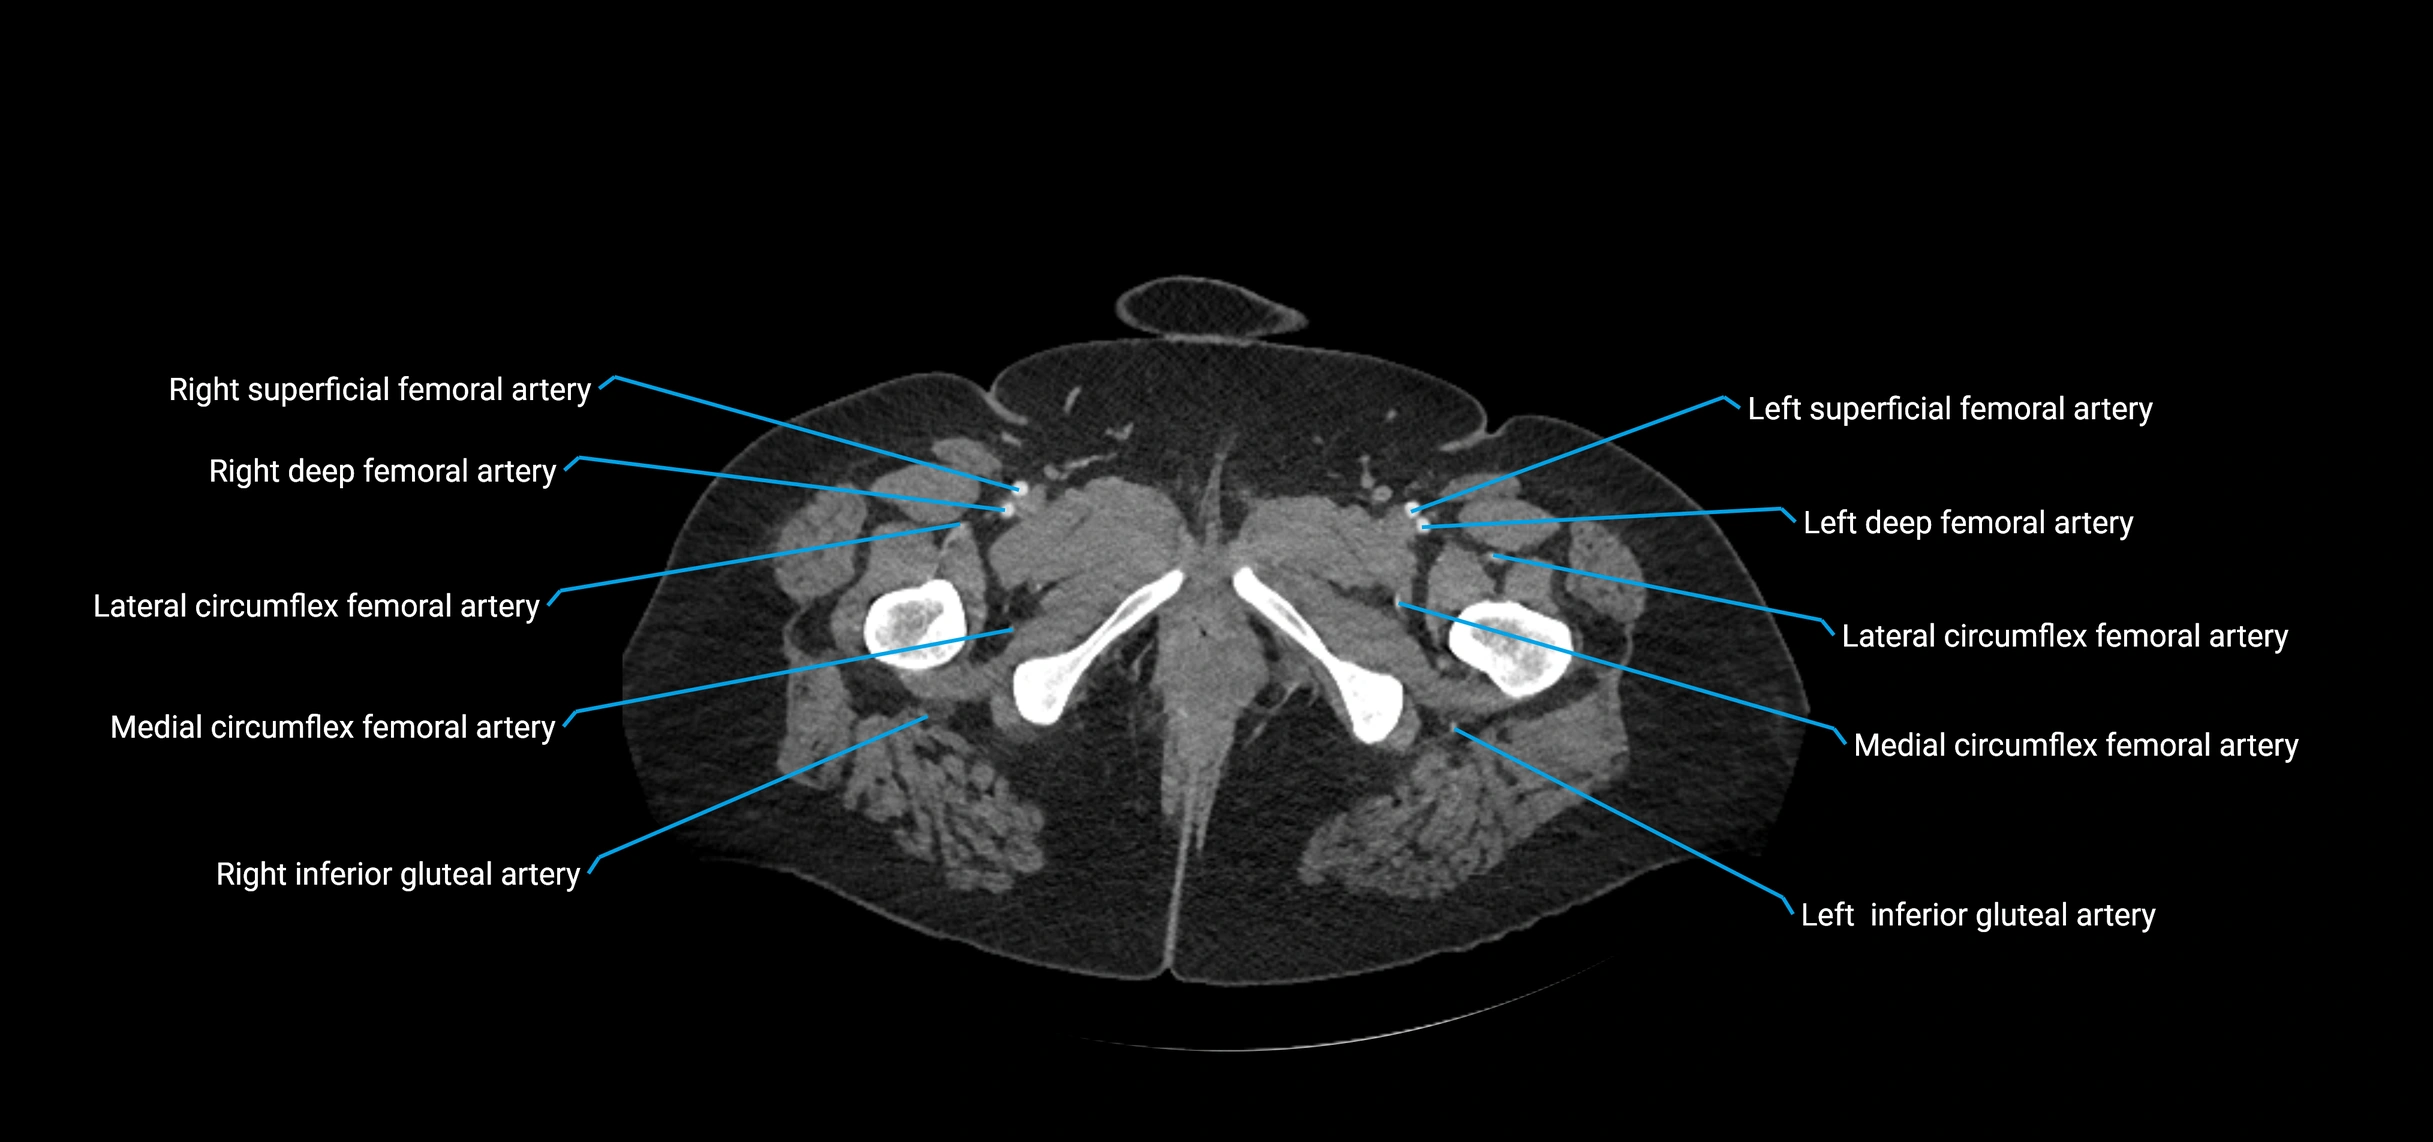

Contrast-enhanced CT (CTA):

• Gold standard for abdominal aortic imaging

• Provides excellent detail of lumen, wall, aneurysm, thrombus, and branch vessels

• Multiplanar and 3D reconstructions help in aneurysm measurement, stent graft planning, and dissection evaluation